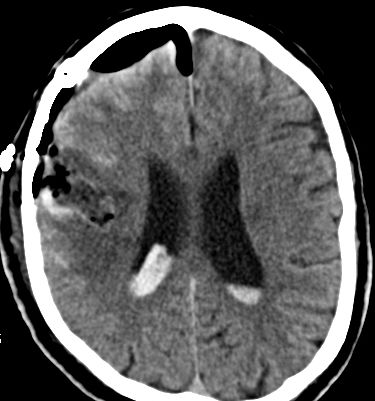

Als schnellste und sicherste Maßnahme gilt das craniale Computertomogramm (CCT). Hier lässt sich eine frische SAB meist zuverlässig darstellen, wobei auch bereits richtungsweisende Befunde, wie das Ausmaß der Blutung und eine eventuelle Lokalisation eines möglichen Aneurysmas bestimmt werden können. Darüber hinaus kann ein Angio-CCT, bei dem zusätzlich Kontrastmittel verabreicht wird und dann die intrazerebralen Blutgefäße gesondert rekonstruiert und dargestellt werden, weitere Informationen liefern. Der sogenannte “Goldstandard” zur Diagnose zerebraler Gefäßmissbildungen ist jedoch die zerebrale Angiographie. Dabei wird mit Hilfe eines speziellen Katheters über die Leisten- oder Armarterie Kontrastmittel gegeben und die zerebralen Blutgefäße hoch selektiv dargestellt. Sollten sich auf dem initialen CCT Zeichen des Hirnwasseraufstaus zeigen, der durch ein Verstopfen der Abflusskanäle durch das neu aufgetretene Blut bedingt ist, ist oft die Anlage einer Hirnwasserableitung nach außen notwendig (externe Ventrikeldrainage).

CT Bildgebung der klassischen subarachnoidalen Blutverteilung nach SAB

Als diagnostische Maßnahme wird in der Regel ein craniales Computertomogramm (CCT) durchgeführt. Intrazerebrale Blutungen lassen sich mit dieser Methode sicher diagnostizieren.